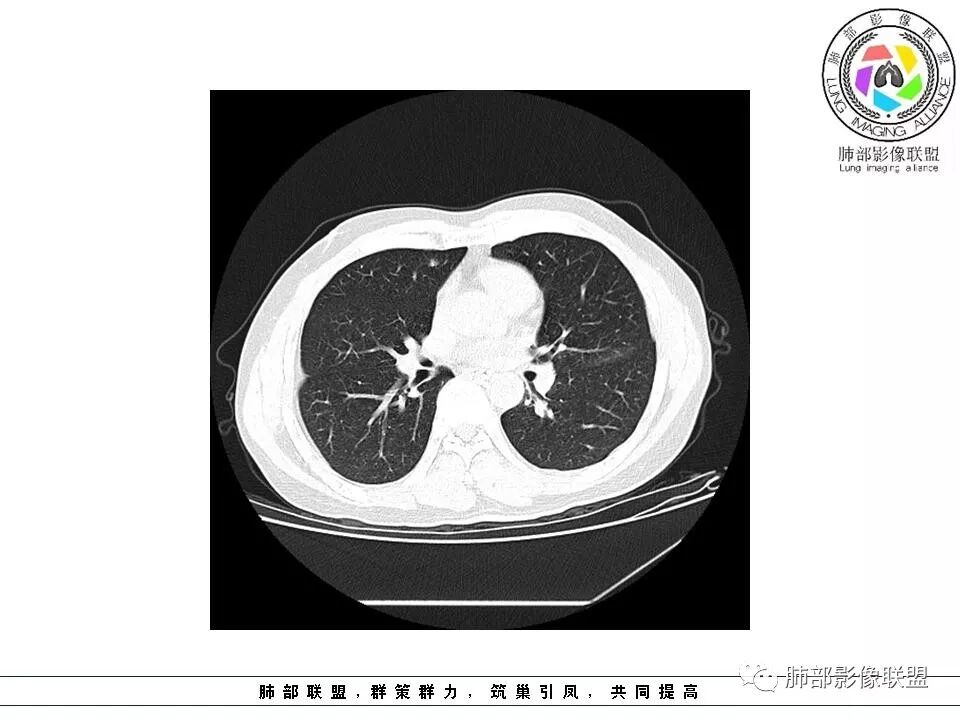

南边:51岁男性,体检发现右肺结节这个年龄段的男性,啥都可以发生,也属于肺癌的高危人群南边:首先是实性还是GGO?好像实性吧